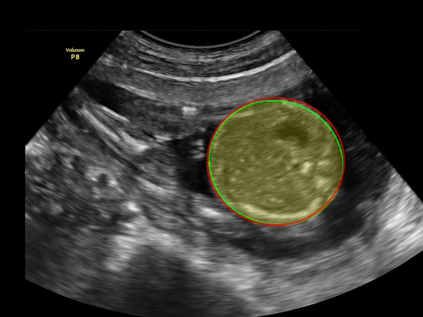

In this paper, we propose an end-to-end multi-task neural network called FetalNet with an attention mechanism and stacked module for spatio-temporal fetal ultrasound scan video analysis. Fetal biometric measurement is a standard examination during pregnancy used for the fetus growth monitoring and estimation of gestational age and fetal weight. The main goal in fetal ultrasound scan video analysis is to find proper standard planes to measure the fetal head, abdomen and femur. Due to natural high speckle noise and shadows in ultrasound data, medical expertise and sonographic experience are required to find the appropriate acquisition plane and perform accurate measurements of the fetus. In addition, existing computer-aided methods for fetal US biometric measurement address only one single image frame without considering temporal features. To address these shortcomings, we propose an end-to-end multi-task neural network for spatio-temporal ultrasound scan video analysis to simultaneously localize, classify and measure the fetal body parts. We propose a new encoder-decoder segmentation architecture that incorporates a classification branch. Additionally, we employ an attention mechanism with a stacked module to learn salient maps to suppress irrelevant US regions and efficient scan plane localization. We trained on the fetal ultrasound video comes from routine examinations of 700 different patients. Our method called FetalNet outperforms existing state-of-the-art methods in both classification and segmentation in fetal ultrasound video recordings.